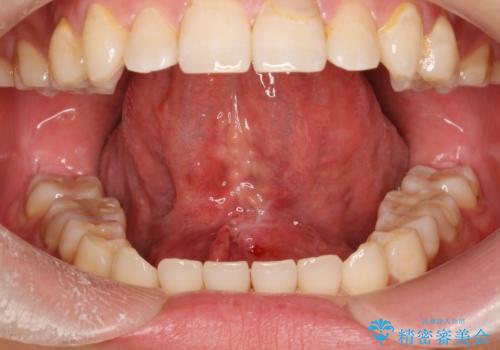

[滑舌を治したい] 舌の小帯の形成術

担当医 大元洋佑

![[滑舌を治したい] 舌の小帯の形成術の症例 治療前](https://seimitsushinbi.jp/wp/wp-content/uploads/2023/11/IMG_8451-500x350.jpg?v=1699614841)

![[滑舌を治したい] 舌の小帯の形成術の症例 治療後](https://seimitsushinbi.jp/wp/wp-content/uploads/2023/11/IMG_8901-500x350.jpg?v=1699614854)